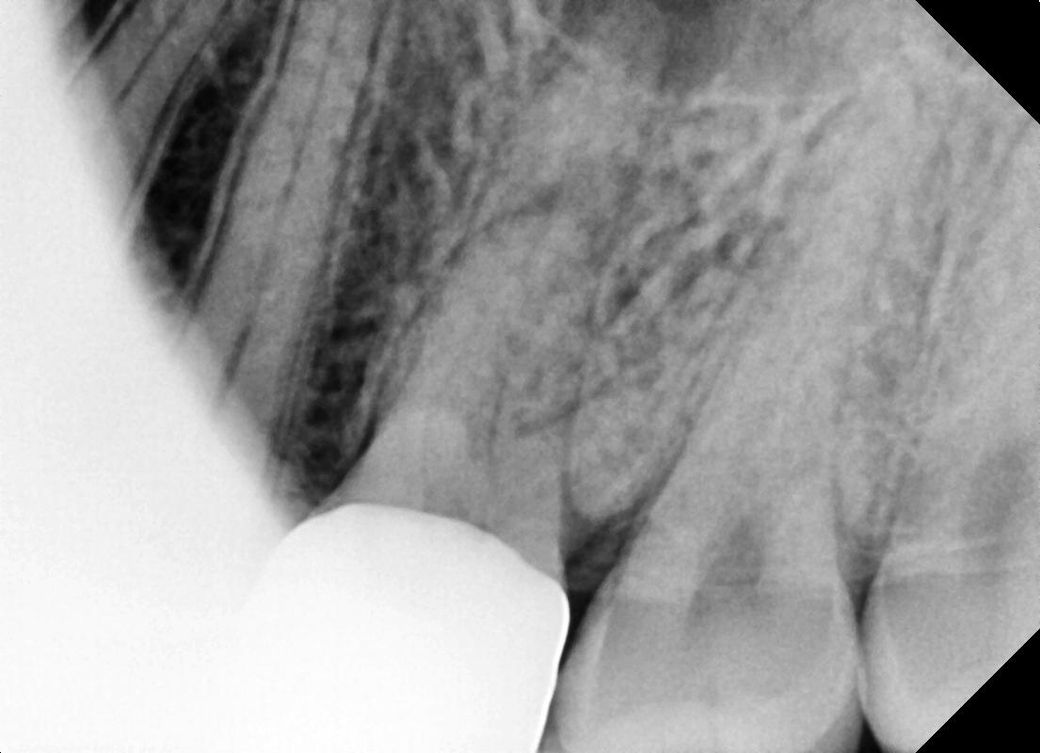

• 1번 째 사진

네 치근단 염증이 있는 상태가 엑스레이 상에서도 확인이 됩니다 크라운 뜯거나 구멍을 내고 신경치료 시도하면 됩니다